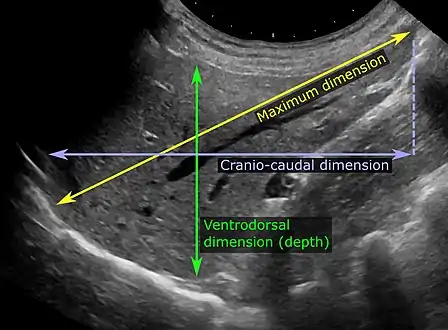

Ultrasonography of liver tumors involves two stages: detection and characterization. Tumor detection is based on the performance of the method and should include morphometric information (three axes dimensions, volume) and topographic information (number, location specifying liver segment and lobe/lobes). The specification of these data is important for staging liver tumors and prognosis. Tumor characterization is a complex process based on a sum of criteria leading towards tumor nature definition. Often, other diagnostic procedures, especially interventional ones, are no longer necessary. Tumor characterization using the ultrasound method will be based on the following elements: consistency (solid, liquid, mixed), echogenicity, structure appearance (homogeneous or heterogeneous), delineation from adjacent liver parenchyma (capsular, imprecise), elasticity, posterior acoustic enhancement effect, the relation with neighboring organs or structures (displacement, invasion), vasculature (presence and characteristics on Doppler ultrasonography and contrast-enhanced ultrasound (CEUS).